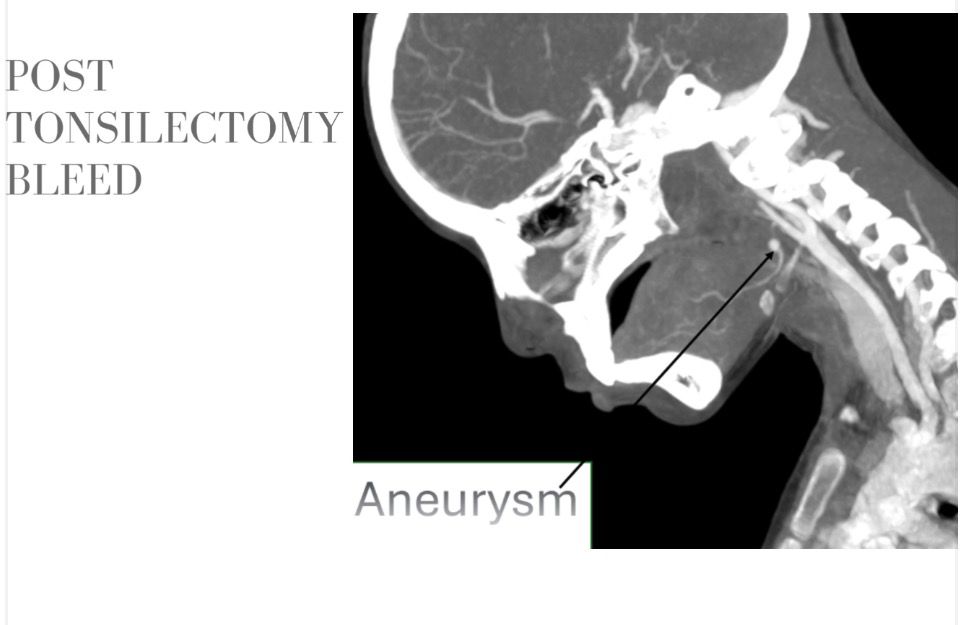

الكشف عن تمدد شرياني نازف

أجرى فريق الأشعة التداخلية الفحوصات والأشعات اللازمة فور وصول الطفلة، والتي كشفت عن وجود تمدد شرياني نازف بأحد الشرايين الرئيسية بالرقبة في جدار الحلق، ما تطلب تدخلا عاجلا عالي الدقة.